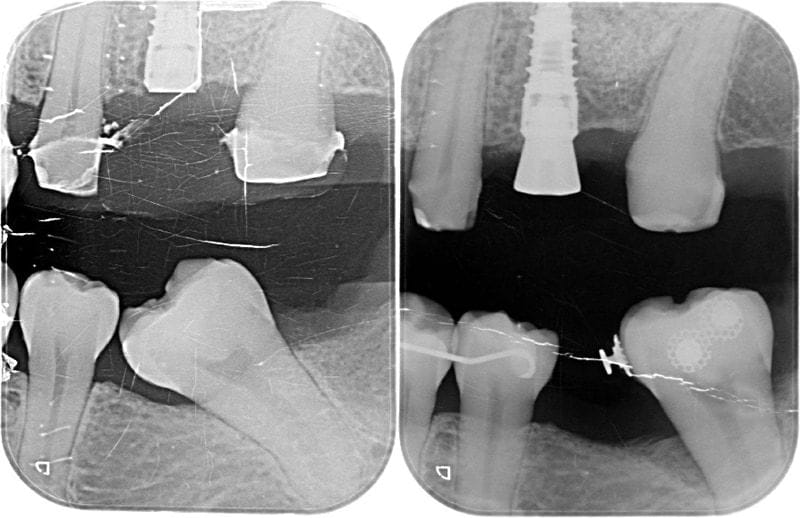

左下區域很早第一大臼齒就缺牙。因為缺牙不補,久了以後齒列空間改變,後面兩顆臼齒往前傾倒,造成吃東西時食物堆積難以清潔的問題。左邊上面後方假牙,時間久遠,密合度已經不佳,這會是清潔的死角,因而造成牙菌斑堆積導致牙齦發炎流血。

圖示:長期缺牙不補導致鄰牙移位與空間喪失,影響咬合更產生食物塞牙縫與牙周問題

全口牙周檢查方面,齒槽骨是有初期流失,只有在主訴區域有比較深的牙周囊袋,屬於全口輕微、局部中度牙周炎。